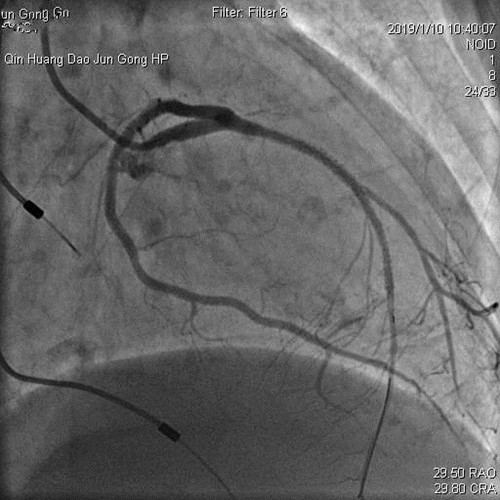

2019年1月10日,心内科王春梅主任、王嘉玮主治医师与北京安贞医院李昭教授共同完成首例冠脉支架内再狭窄药物球囊扩张术。手术的成功,对心内科介入手术的开展和医疗技术的提升具有重要意义。

患者杨某,女,74岁,因发作性胸闷到军工医院就诊。患者曾先后在某医院经冠脉植入过4枚支架及心脏永久起搏器,但是胸闷症状仍然没有解除。因杨某高龄、反复心梗、心衰,咨询多家医院均表示仅能药物保守治疗,拒绝为其行介入治疗。患者家属携带既往病历资料来军工医院咨询,心内科主任王春梅详细询问病情,积极与北京安贞医院李昭主任联系,详细查阅患者既往病历影像资料,考虑患者目前胸闷症状为前降支支架内再狭窄所致,有多次狭窄病变(病历资料显示狭窄病变为前降支两枚支架连接处的狭窄,既往因连接处狭窄已通过重叠植入支架治疗)。

王主任考虑患者高龄,反复心梗,心功能差,手术风险高,难度大。患者前降支血管承担着几乎整个心脏的供血,再狭窄部位为前降支的关键位置,如果手术过程稍有不慎,将会危及生命,后果将不堪设想。

经过反复沟通,向患者及家属详细讲解手术过程、风险及并发症。家属对军工医院表示信任,同意使用药物球囊治疗狭窄病变。经过近1小时的手术,成功为患者放入了药物球囊。出院2周后医生随访,张某病情平稳,无胸闷、胸痛症状。患者和家属对军工医院心内科王春梅主任勇于担当和技术精湛的医生团队表示感谢。